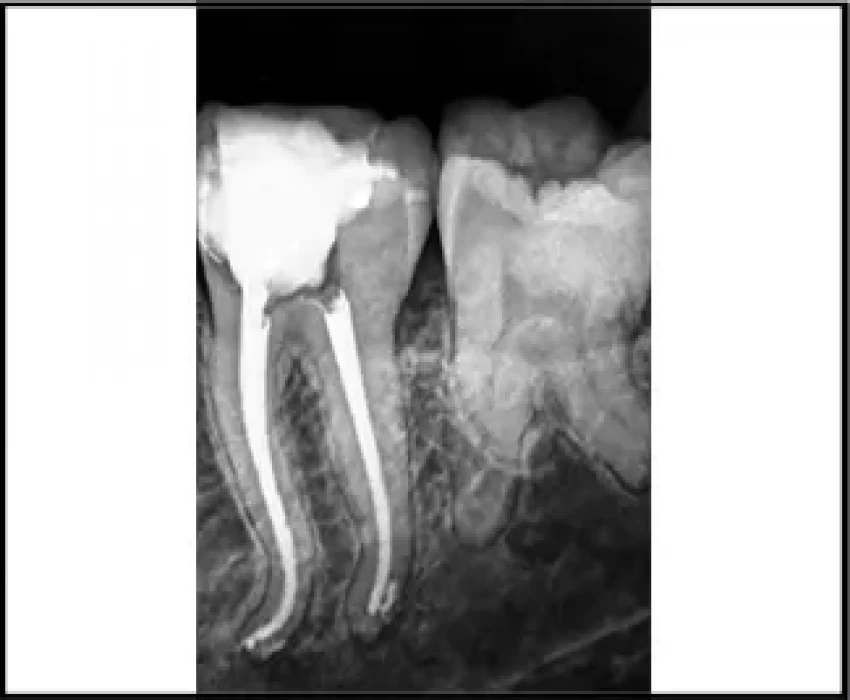

Periapical radiographs are still the most widely used method for determining root canal morphology before endodontic treatment. Accurate detection of complex canal morphology on X-ray is necessary to avoid missing root canals during treatment.

Following the SLOB rule in radiography, changing the horizontal angulation of the X-ray beam cone can, to a large extent, help in identifying and understanding the root canal anatomy. It makes it easier to place the newly found canal, lingual or buccal to the previously identified landmarks.

Along with visualizing anatomy on the radiograph, clinical accessibility and visibility are much needed for complete debridement. Complete de-roofing of the pulp chamber along with the use of sodium hypochlorite for locating canal orifices are the most basic and simplest step to keep in mind to make our job easier and results, better. Magnification of the working field can enhance the visual fields multifold and improved visibility implies improved techniques. The Dental operating microscope is necessary for the detection of extra canals.

Various atypical anatomy calls for improvised techniques of debridement, preparation, and obturation to ensure a proper seal that is required for a successful endodontic treatment. An endodontic file should be used, which adapts to the natural morphology of the root canals and efficiently cleans it.